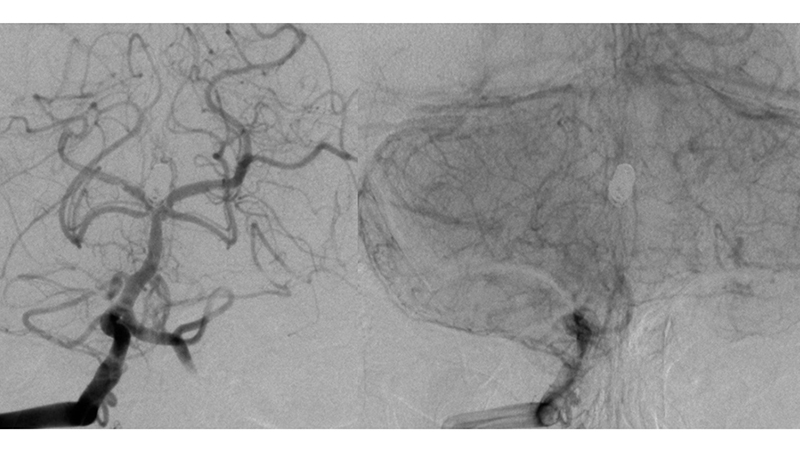

Εικόνα 4: Έχουν τοποθετηθεί τα δύο stents και έχει γίνει η πλήρωση του ανευρύσματος με coils.

Εικόνα 5, 6: Πλήρης απόφραξη του ανευρύσματος με Y-stenting και coils, αμέσως μετά τον εμβολισμό.

Εικόνα 7, 8, 9: Πλήρης σταθερότητα του αποτελέσματος 2 χρόνια μετά, χωρίς εικόνα επανασηραγγοποίησης.